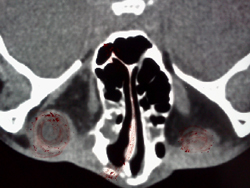

↓事故後の3DCTです

鼻の骨がなくなりました

左眼球がつぶれ鼻中隔が曲がりました↓